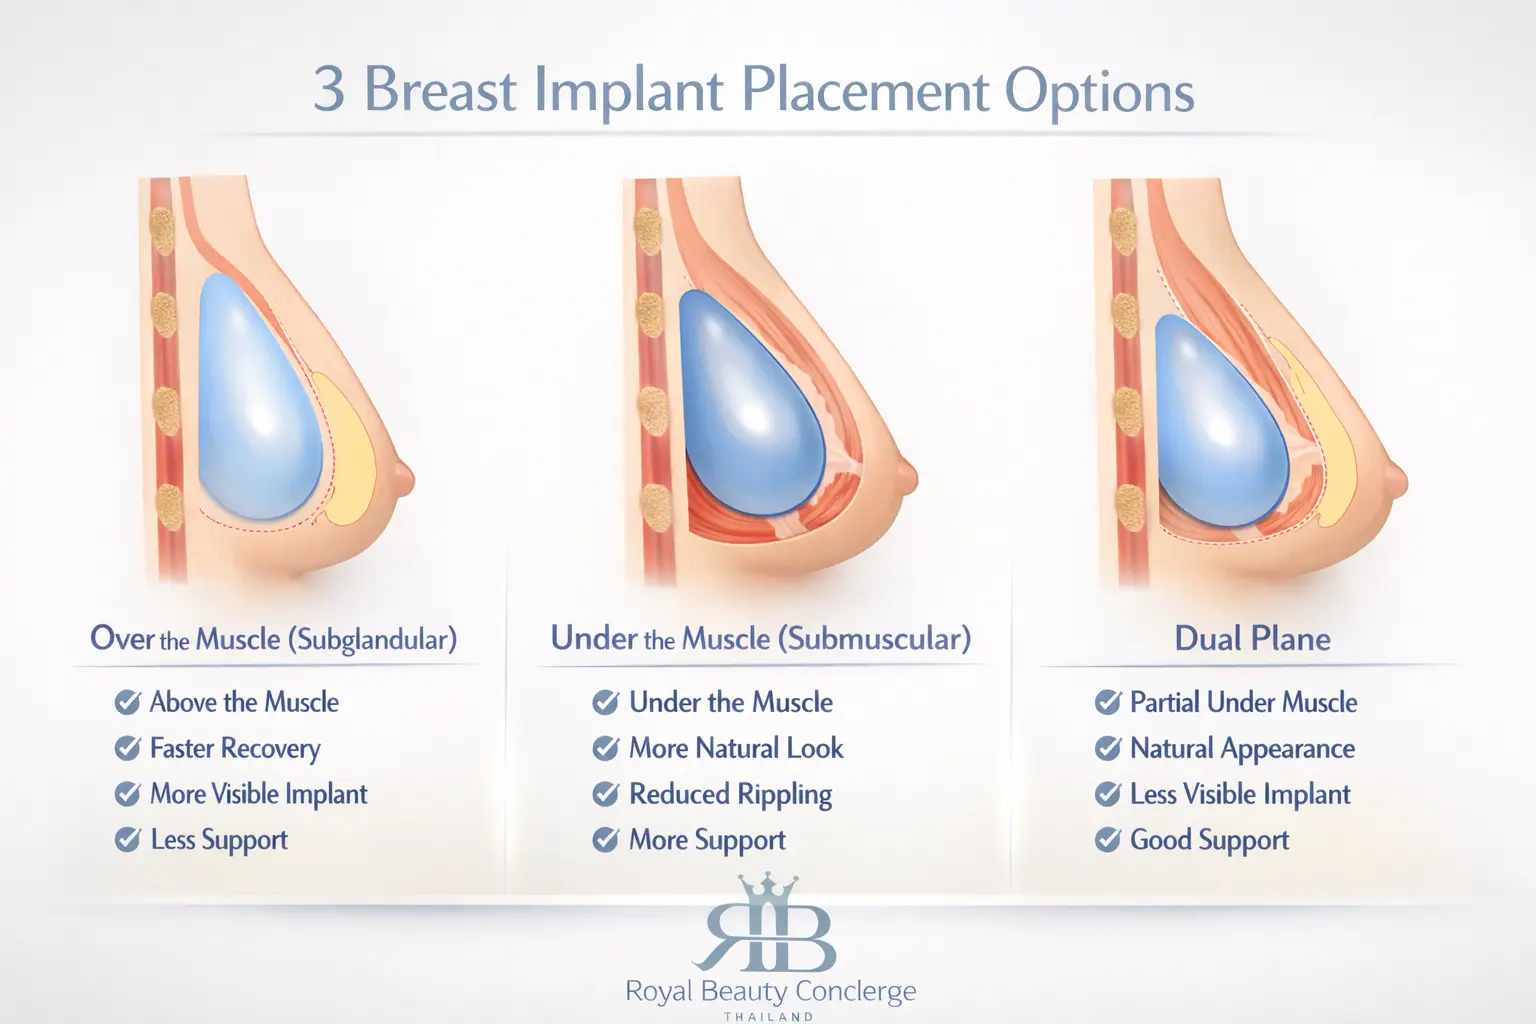

Treatment planning may involve different implant types, implant profiles, implant placement techniques, and incision options, depending on your anatomy, tissue characteristics, and the look you want to achieve.

The right plan depends on your anatomy, skin and tissue characteristics, starting breast volume, implant choice, implant placement, and incision design. A good result is not only about size. It is also about proportion, softness, cleavage, upper fullness, and how the implants sit on your frame.

Selected patients with enough natural tissue coverage and goals that suit this position.

Patients who may benefit from more implant coverage in the upper breast.

Patients who need a more tailored balance between coverage and breast shape.